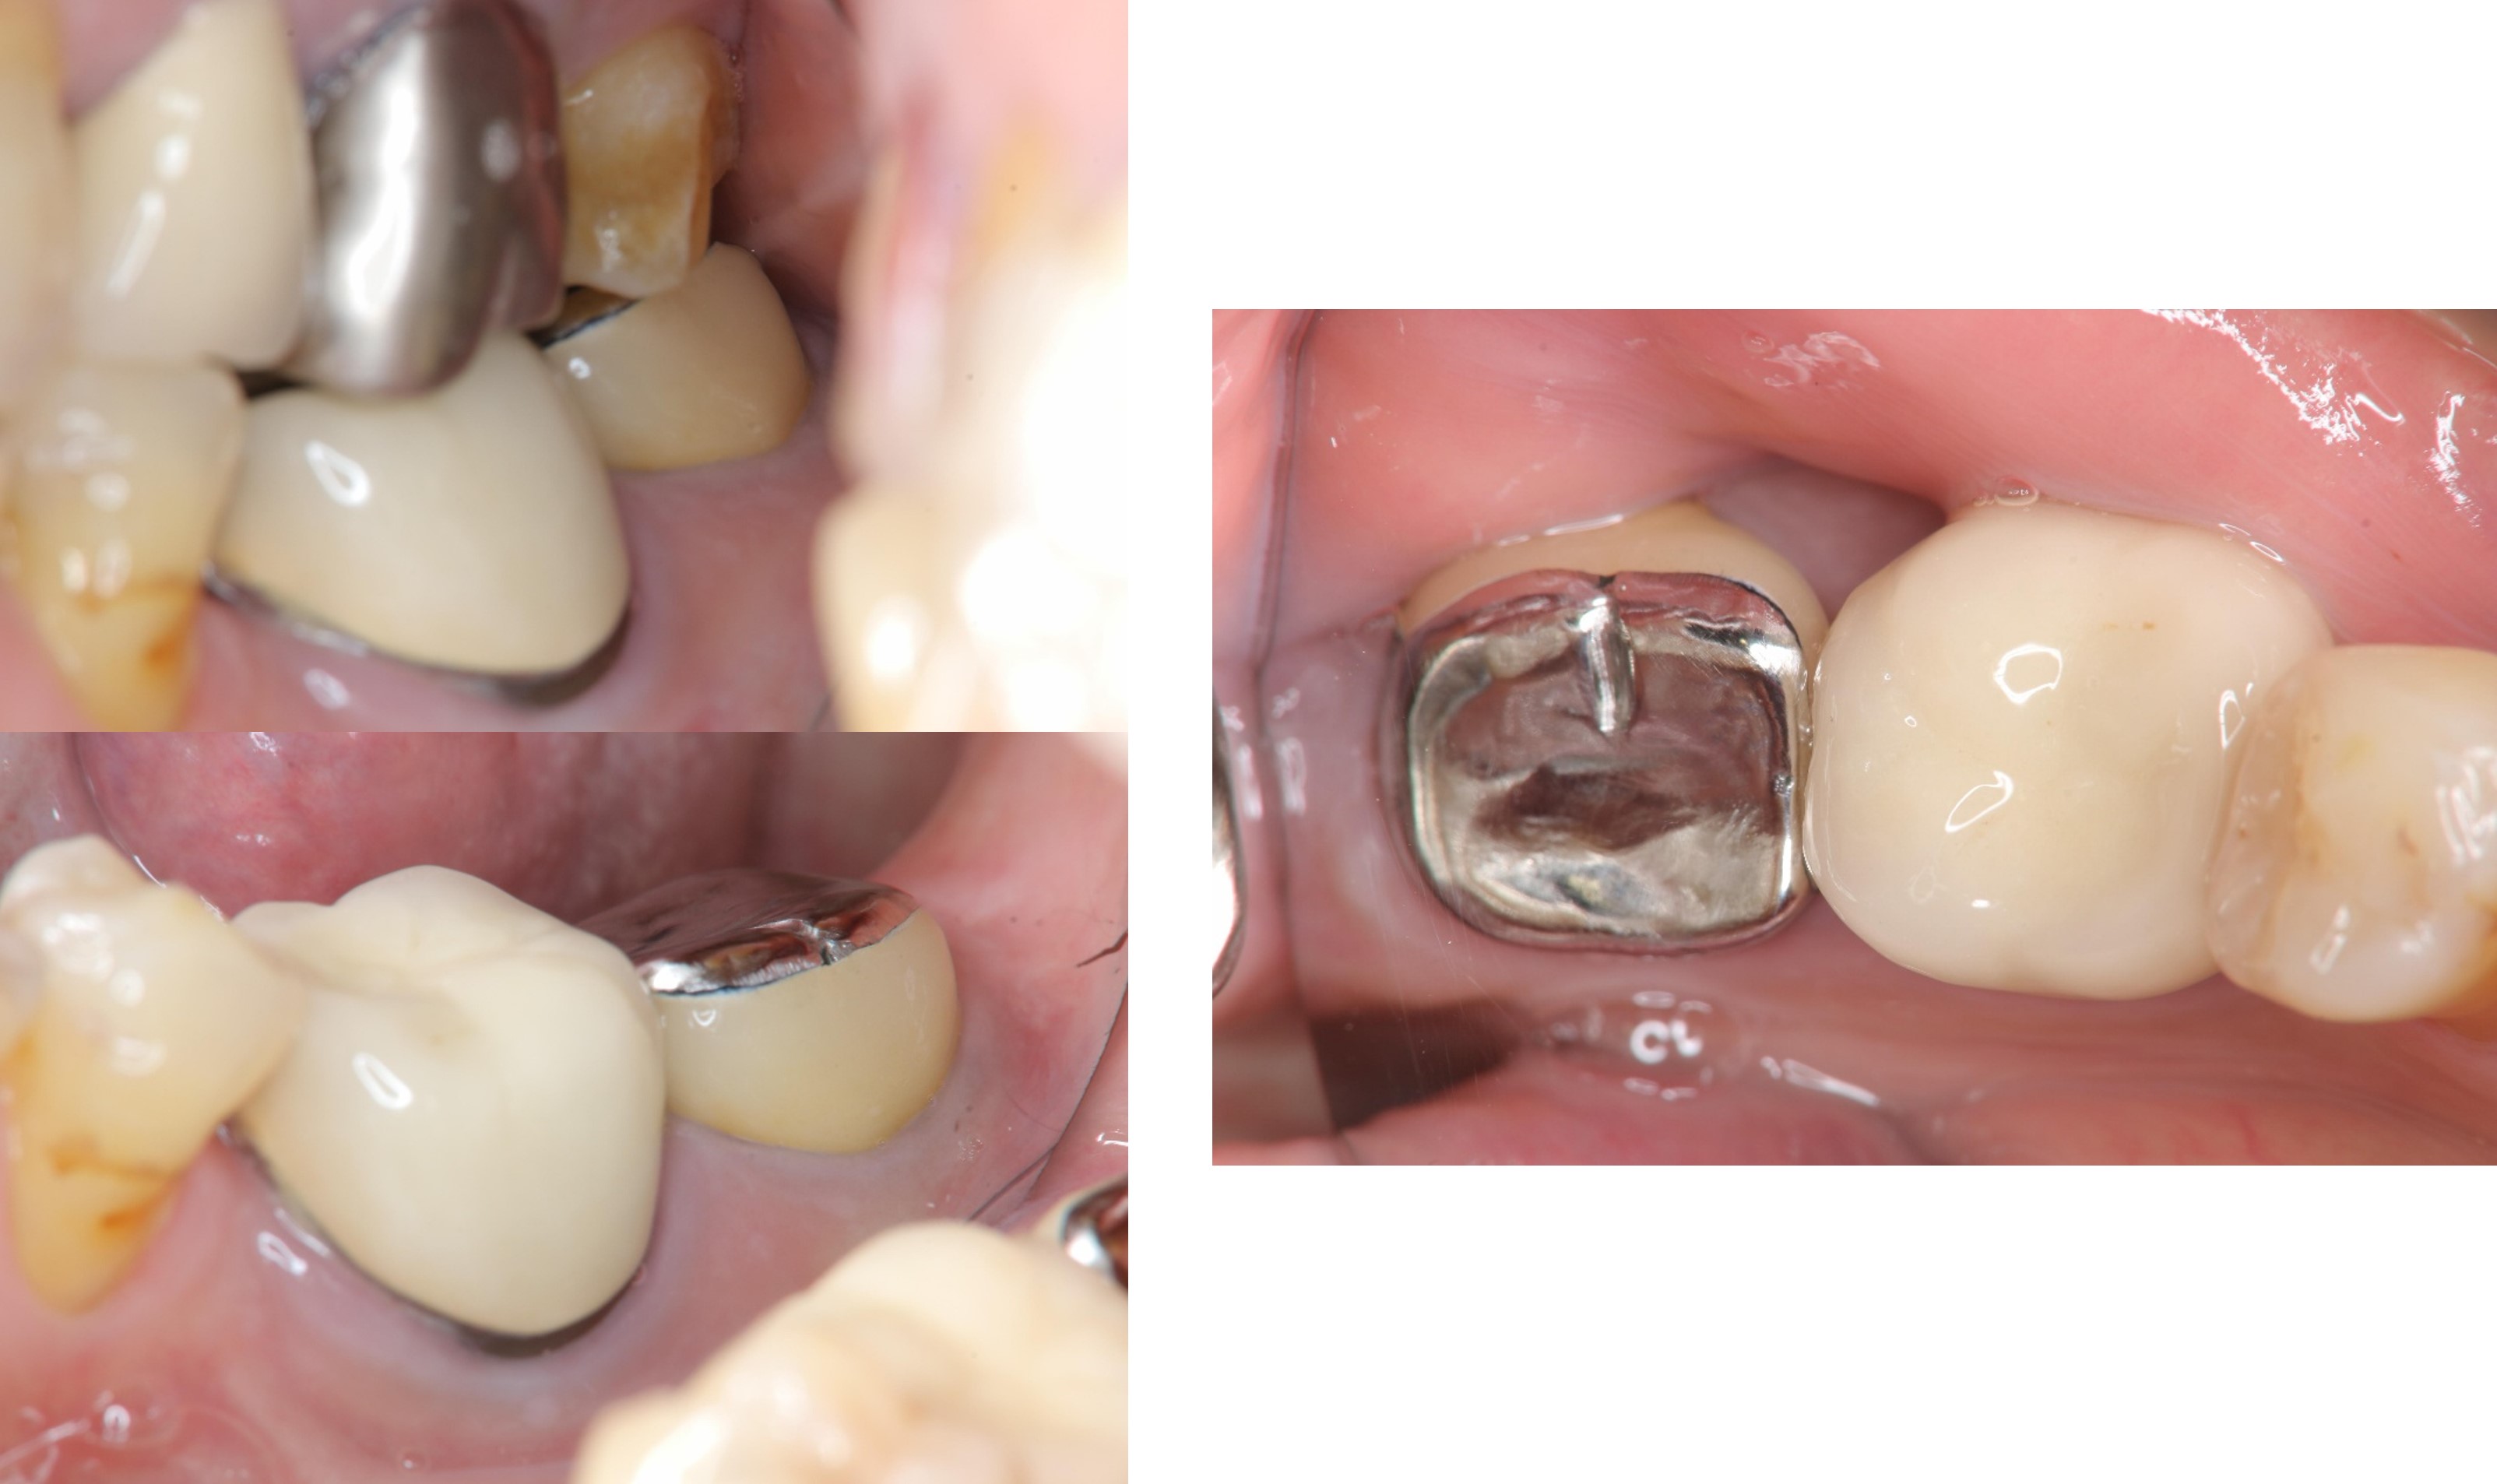

治療前,左下第二大臼齒假牙常脫落,前來求診

之前已根管治療

牙冠增長手術

牙齒印模前追蹤